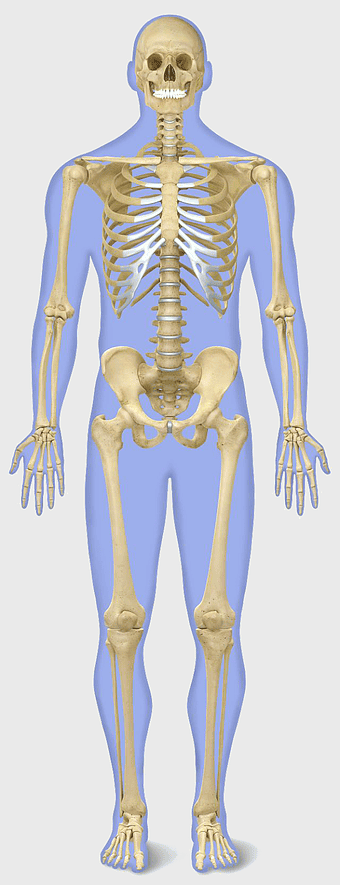

human skeleton illustration, skeletal system anatomy, axial skeleton structure, appendicular skeleton bones, human skeletal framework, skeletal joint connections, bone structure analysis -

human skeleton, bone structure, nervous system anatomy, joint function, skeletal framework, anatomical illustration, human body composition -

Human skeleton, human body anatomy, standing skeleton, bone structure, skeletal system, medical illustration, human anatomy study -

human skeleton illustration, white skeleton decor, rib cage anatomy, vertebral column drawing, skeletal system diagram, medical skeleton art, human bones structure -

Human skeleton, rib cage anatomy, upper limb bones, joints in human body, skeletal structure analysis, vertebral column details, anatomical illustration study -

human skeleton illustration, human anatomy bones, skeletal system diagram, human body structure, anatomical reference, medical illustration, educational skeleton image -